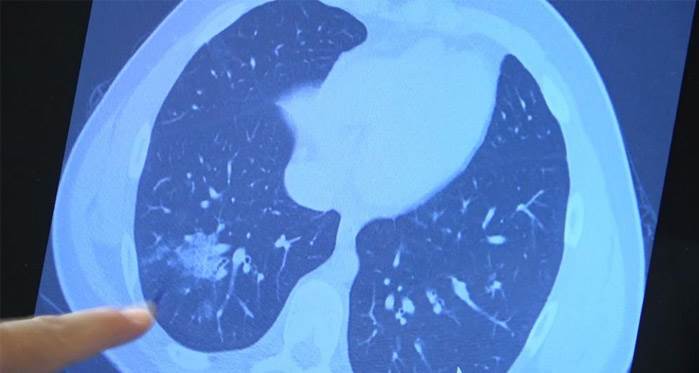

Haberler >Gündem haberleri » Koronavirüsün çocuklardaki tehlikesi büyüyor!